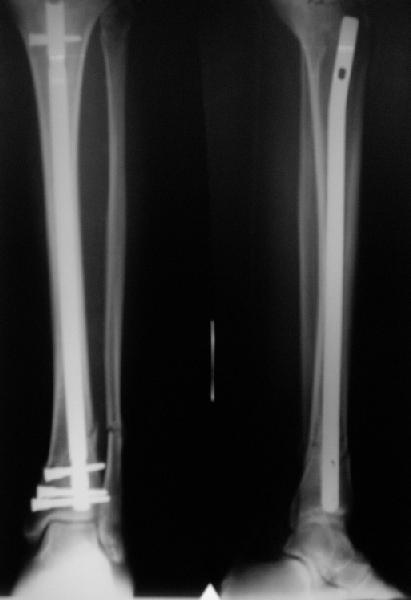

Отправитель: Alexander Chelnokov 21 Май 2006, 23:21

TDVC> Very interesting application, but is the final position in a

TDVC> little distal varus with some fibula distraction?

At least both the ankle mortise and tibial alignment look acceptable, don't they?

TDVC> Would that have been eliminated by fibula plating?

I am just trying to illustrate that prevention of 1)tibial valgus and 2)loss of reduction can be provided without fibular plating. Small changes of conventional nailing techniques allow to maintain reduction of the tibia reliably without adjunctive fibular stabilization.

In delayed cases acute length restoration performed only in the tibia may leave the fibula shortened thus change the mortise. So it is reasonable to restore length of both bones simultaneously by distractor and fix the fibula not with open reduction and plating but just by a single perQ screw. Example attached.